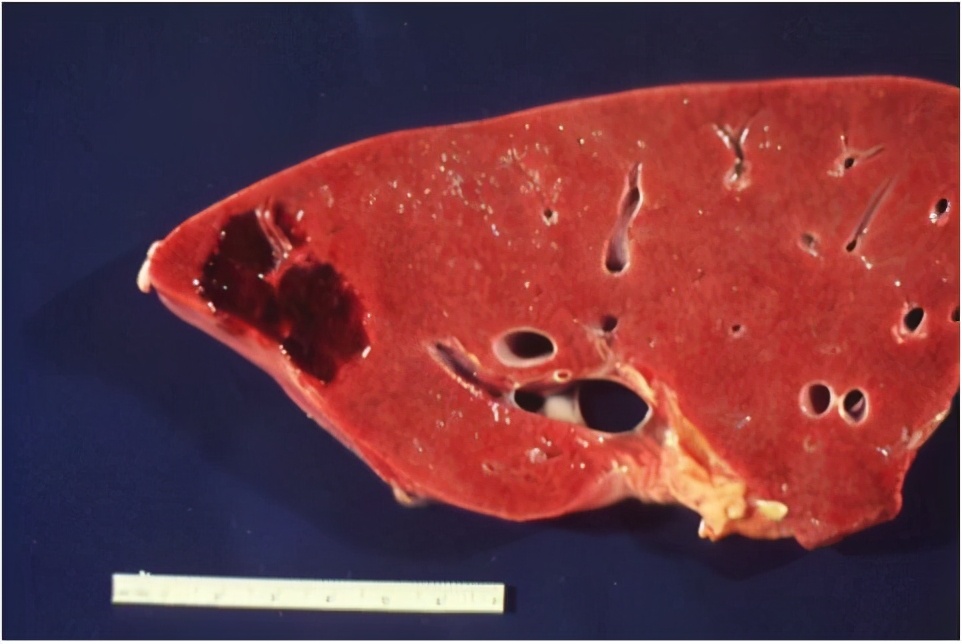

在做过肝血管瘤手术的患者现场,您可以看到,我们是边界清楚的、表面上覆盖了一层薄薄的、颜色比较深的、囊状的、可能还有蒂的“瘤”。

切开来以后,可以看到红棕色的海绵状结构,有时可能会出血,还会发现有疤痕和钙化,这说明我们可能在某个时期合并过炎症。

为了看得更细,切片可以放在显微镜下观察,能够看到更细微的结构,主要是有大小不等的海绵状血管腔,腔的内表面的内皮细胞内充满着血液,可能会发现血栓、结节和钙化。